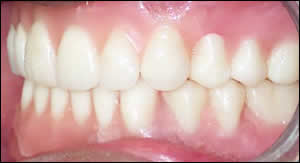

Fig 9: A frontal view of centric occlusion .The upper denture in place. The lower overdenture clipped into place.